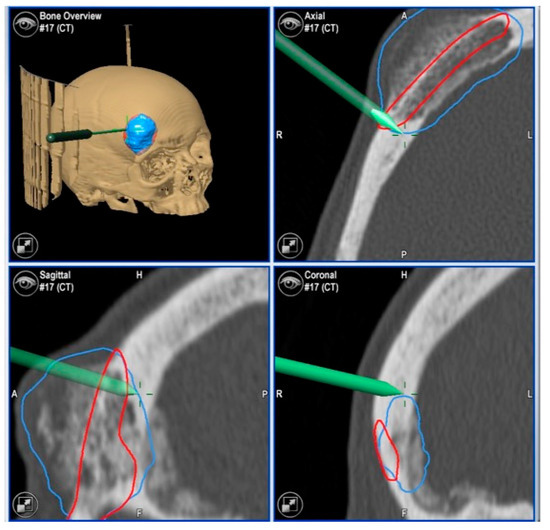

| 1 | 53/F | L/25 mm | Y | 4 mo | Dystopia | N | CT, MRI | Supraorbital rim, orbital roof | Intraosseous venous malformation | - | Resection + reconstruction | Y | Y | 1st, 2nd, 3rd | Coronal | Y | Piezoelectric device | N | PEEK prosthesis | 7 y/N |

| 2 | 54/F | R/33 mm | Y | 9 y | N | Y | CT, MRI | Frontal bone, orbital roof | Intraosseous venous malformation | - | Resection + reconstruction | Y | Y | 1st, 2nd, 3rd | Coronal | Y | Piezoelectric device | N | PEEK prosthesis | 6 y/N |

| 3 | 36/F | L/19 mm | Y | 6 mo | N | N | CT, MRI | Zygoma | Arteriovenous malformation | - | Resection + reconstruction | Y | Y | 1st, 2nd, 3rd | Transconjunctival + blepharoplasty + maxillary vestibular | Y | Piezoelectric device | N | PEEK prosthesis | 5 y/N |

| 4 | 47/M | L/30 mm | N | 2 y | N | N | CT | Zygoma | Intraosseous venous malformation | - | Resection + reconstruction | Y | Y | 1st, 2nd, 3rd | Transconjunctival + lateral canthotomy + maxillary vestibular | Y | Piezoelectric device | N | PEEK prosthesis | 6 y/N |